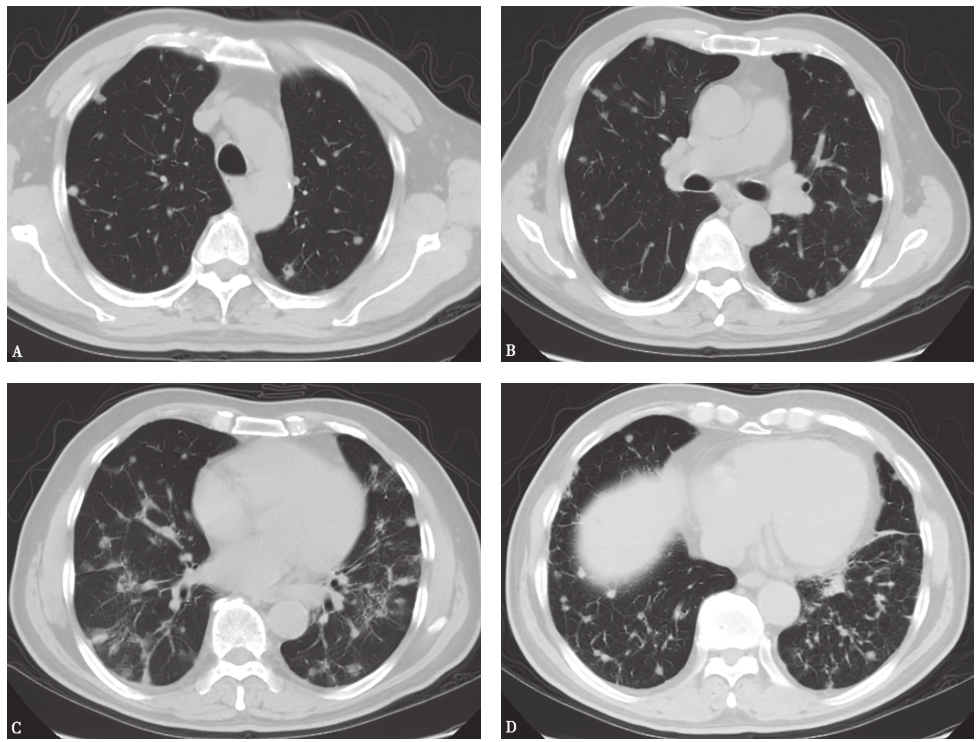

2013年3月5日复查胸部CT示双肺结节影,伴多发纤维索条样病变(图2)。

图2病例Ⅰ胸部CT表现(2013-03-05)

病例Ⅰ入院后体温正常,咳嗽、气短症状较前好转,于2013年8月24日复查胸部CT,见肺部病变较前明显吸收(图4);病例Ⅱ口服伊曲康唑1个月后出现甲状腺功能低下而停用,发病7个月后复查胸部CT,见双肺结节亦明显吸收(图5)。

图4病例Ⅰ治疗后复查胸部CT表现

2013年3月5日查胸部CT(A、C、E)示双肺多发结节性病变伴纤维索条影;2013年8月24日复查胸部CT(B、D、F)示双肺结节样病灶较前明显吸收

图5病例Ⅱ治疗后复查胸部CT表现

2013年1月28日查胸部CT(A、C、E)示双肺多发结节性病变;发病7个月后复查胸部CT(B、D、F)示双肺结节影较前明显吸收